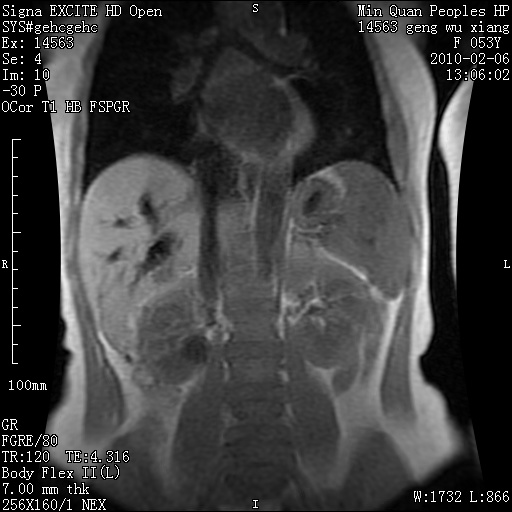

标题: MRI2762:胆道梗阻原因?

f,53y,全身黄染多日。

高位胆道梗阻 胆管癌可能性大

支持 高位胆道梗阻 胆管癌可能性大。